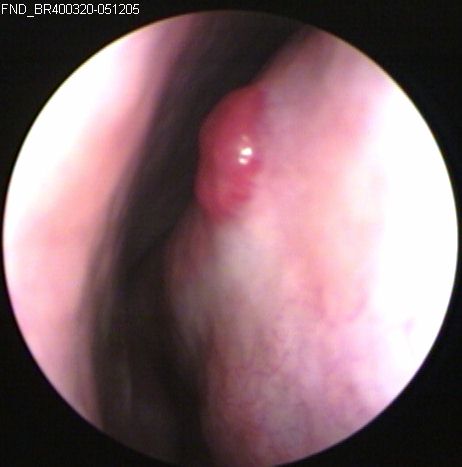

JFC Otitis media crónica con afectación de N.Facial